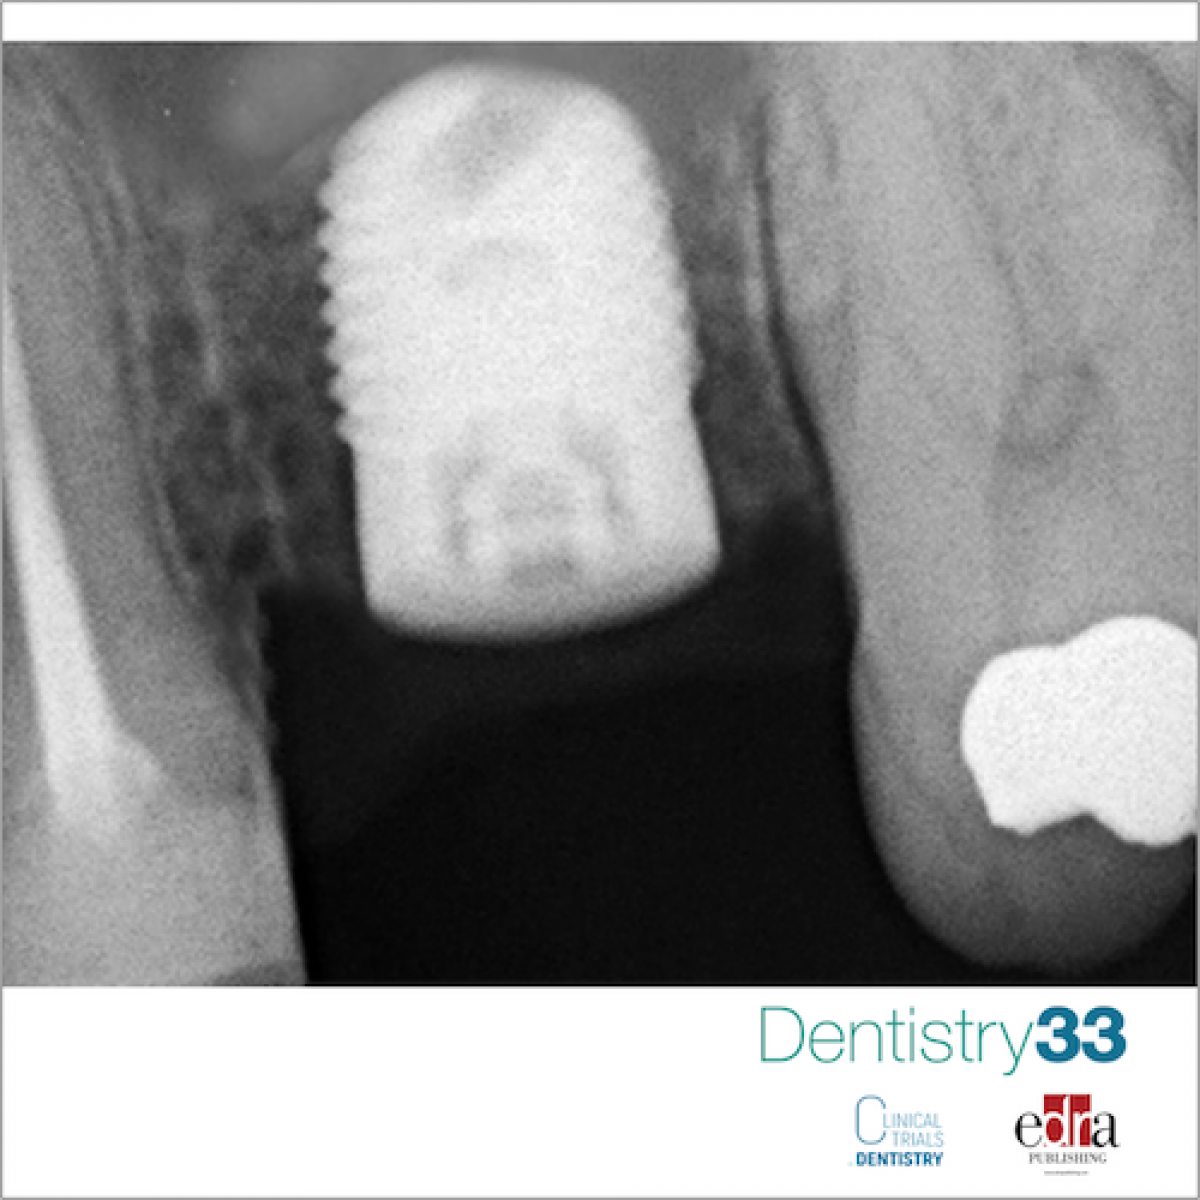

Early implant loading in the atrophic posterior maxilla: an 11-year randomised controlled trial of 1-stage lateral versus crestal sinus lift and 8-mm-long hydroxyapatite-coated implants

To compare 10- to 16-mm-long implants inserted into maxillary sinuses augmented with a lateral approach versus 8-mm-long implants placed in crestally augmented sinuses, both loaded early after 45 days.

Forty partially or fully edentulous patients having 3 to 6 mm of residual crestal bone height and at least 4 mm thickness below the maxillary sinuses were randomised according to a parallel group design to receive either one to three 10- to 16-mm-long hydroxyapatite- coated implants (20 patients) after lateral sinus lift with 50% anorganic bovine (Bio-Oss) and 50% autogenous bone, or 8-mm-long implants (20 patients) after crestal sinus lift with autogenous bone. All implants were submerged and left to heal for 45 days before being loaded. Within one week after abutment connection, implants were loaded with screw-retained fully acrylic provisional prostheses. Definitive metal-ceramic prostheses were provisionally cemented 45 days after abutment connection. Outcome measures were: prosthesis or implant failure, any complications, and radiographic peri-implant marginal bone level changes. In addition, the stability of individual implants was assessed via Osstell and Periotest by blinded outcome assessors, although Periotesting was discontinued after the fifth year in function. All patients were followed up to 11 years after loading.

One patient per group dropped out. One implant failed in the short implant group versus five implants in three patients from the longer implant group, the difference being not statistically significant (difference in proportions: 0.11; P = 0.604; 95% CI = -0.15 to 0.36). Three prostheses in the long implant group could not be fitted or were replaced versus one crown on short implants, the difference being not statistically significant (difference in proportions: 0.11; P = 0.604; 95% CI = -0.15 to 0.36). Six complications occurred in six patients from the short implant group versus ten complications in seven patients from the long implant group, the difference being not statistically significant different (difference in proportions: 0.053; P = 1.000; 95% CI = -0.265 to 0.357); however, two major postoperative complications occurred in the longer implant group: one abscess and one sinusitis, both of which determined the complete failure of the treatment in two patients (four implants lost). After 11 years, a total of 1.26 mm of peri-implant marginal bone had been lost at long implants and 0.64 mm at short implants, and the difference between the two groups was statistically significant (difference: 0.62 mm, 95% CI = 0.25 to 0.99; P=0.002).

In atrophic maxillary sinuses with a residual bone height of 3 to 6 mm, 8-mm short implants placed in simultaneously crestally lifted sinus might be a preferable choice than one-stage lateral sinus lift for placing longer implants, since the former appear be associated with lower morbidity. Implants placed with an insertion torque superior to 35 Ncm can be early loaded at 6 weeks.